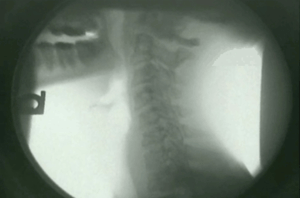

The next step involves the use of an imaging study called Digital Motion X Ray, or DMX that gives unprecedented insight into the biomechanics of the spine. DMX studies allow us to pinpoint the exact location and extent of damage to spinal ligaments.

DMX has been developed purely as a diagnostic tool, and uses imaging protocols that create a bright white background against which the bones are easily visible.

When you watch a DMX study, you are seeing an image of the patient in the lower left hand corner. You’ll see them move their head up and down, left and right, and side to side.

As the patient moves, DMX allows us to clearly visualize the movement of the bones in the spine. In patients who have suffered damage to the spinal ligaments, abnormal motion is present.

You will often see one vertebrae slide several millimeters in relation to another, indicating tearing of the anterior or posterior longitudinal ligaments.

We will often find that the intervertebral foramen (the holes in the spine where the nerves exit) close down in flexion or extension be- cause the capsular ligaments that hold them open have been torn.